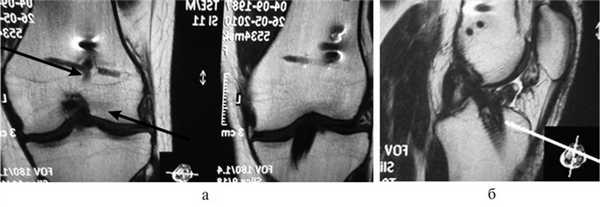

При МРТ-исследовании у 86 пациентов с острой травмой коленного сустава мы обнаружили в 39 (43%) случаях не только мягкотканные повреждения связочного аппарата, менисков, хряща, но и участки с контузией губчатой части мыщелков бедра и большеберцовой кости разной степени выраженности. Без применения МРТ такие травматические изменения (контузия) губчатой кости ранее вообще не диагностировались никакими другими методами. Мы обратили внимание на то, что все эти пациенты в отличие от остальных пациентов с острой травмой коленного сустава жаловались на выраженный болевой синдром и имели длительный период сгибательно-разгибательной контрактуры коленного сустава. В таких случаях мы откладывали оперативное лечение до стихания острого периода и болевых ощущений (рис. 3).

Рис. 3. МРТ-изображение коленного сустава в Т1- и Т2-режимах с участками острых контузионных изменений в мыщелках бедренной кости и наружном мыщелке большеберцовой кости (указано стрелками).

С помощью МРТ-контроля мы обнаружили, что внутрикостные кровоизлияния в мыщелках бедра и большеберцовой кости регрессировали примерно через 2—4 мес после травмы при условии целенаправленного медикаментозного и физиотерапевтического лечения именно этих контузионных явлений. По мере того как, по данным МРТ, костная ткань становилась нормальной, уменьшались болевой синдром и болевая защитная контрактура коленного сустава, возникала более благоприятная ситуация для дальнейшего оперативного лечения. И только на этом этапе всем 39 пациентам была проведена реконструкция ПКС из аутотканей по стандартным артроскопическим методикам.